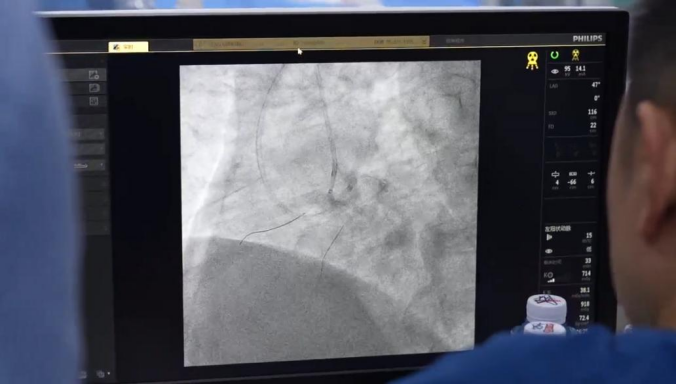

近日,山东南郊医学研究院胡涛心血管病研究中心成功为一名49岁女性患者实施高难度冠脉介入手术,攻克了前降支慢性闭塞(CTO)这一“冠心病最后的堡垒”。

患者因阵发性胸闷、气短入院,冠脉病变极重。虽然此前已成功处理右冠近段狭窄,但前降支CTO病变更为棘手:入口难以辨识,血管内超声无法探及,且闭塞段出口纤细,常规正向介入尝试屡屡受阻。关键时刻,胡涛院长果断转换策略,凭借精湛的逆向介入技术,从侧支循环逆向精准寻径,最终成功打通前降支闭塞血管,恢复了心肌血流。